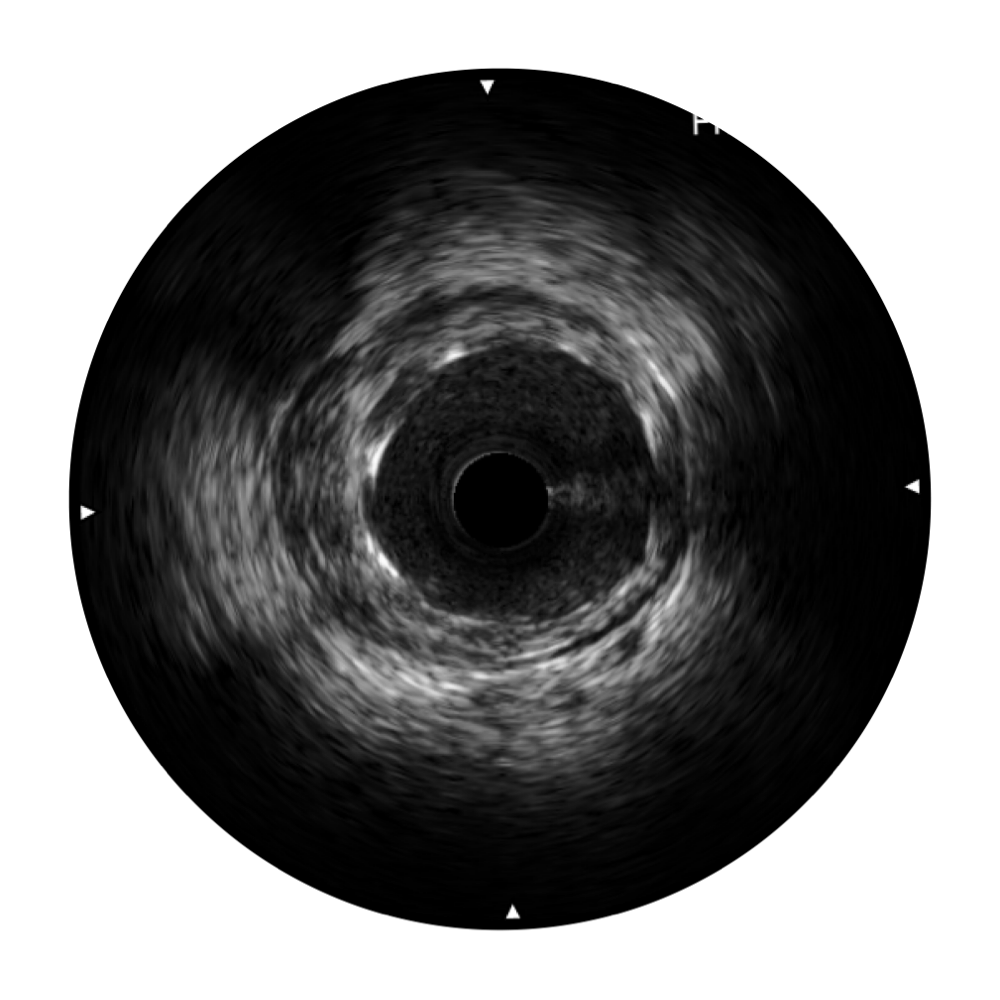

环球UG官网宽频IVUS图像

传统IVUS图像

对比传统IVUS导管成像,环球UG官网宽频IVUS图像的近场支架梁显影更细腻,远场中膜外血管仍清晰可辨,兼顾远中近,兼顾分辨力与穿透深度